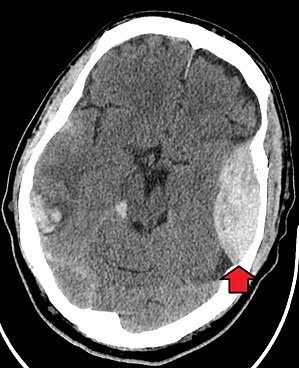

1 จงให้การวินิจฉัยในผู้ป่วยรายนี้